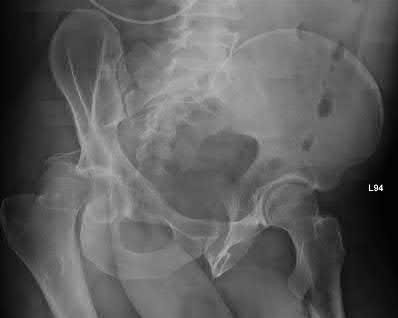

A 44-year-old male presents after being struck by a car. He is hypotensive, and has an obvious open tibia and a closed femoral shaft fracture. A pelvic radiograph is obtained and shown in Figure A. A representative CT scan image in shown in Figure B. The patient is placed in a pelvic binder, and his blood pressure normalizes with crystalloid and a blood transfusion. He then undergoes pelvic angiography, and his internal iliac artery is embolized. Which of the following definitive treatment options is most appropriate in this case?

The radiographs and CT scan show a fracture pattern consistent with an APC-III injury. This is most appropriately treated with pubic symphysis ORIF with a multi-hole plate and posterior iliosacral screw fixation.

APC-III pelvic ring injuries are associated with with disruption of the anterior and posterior SI ligaments (SI dislocation) as well as disruption of

sacrospinous and sacrotuberous ligaments. They are commonly associated with vascular injury and retroperitoneal bleeding.